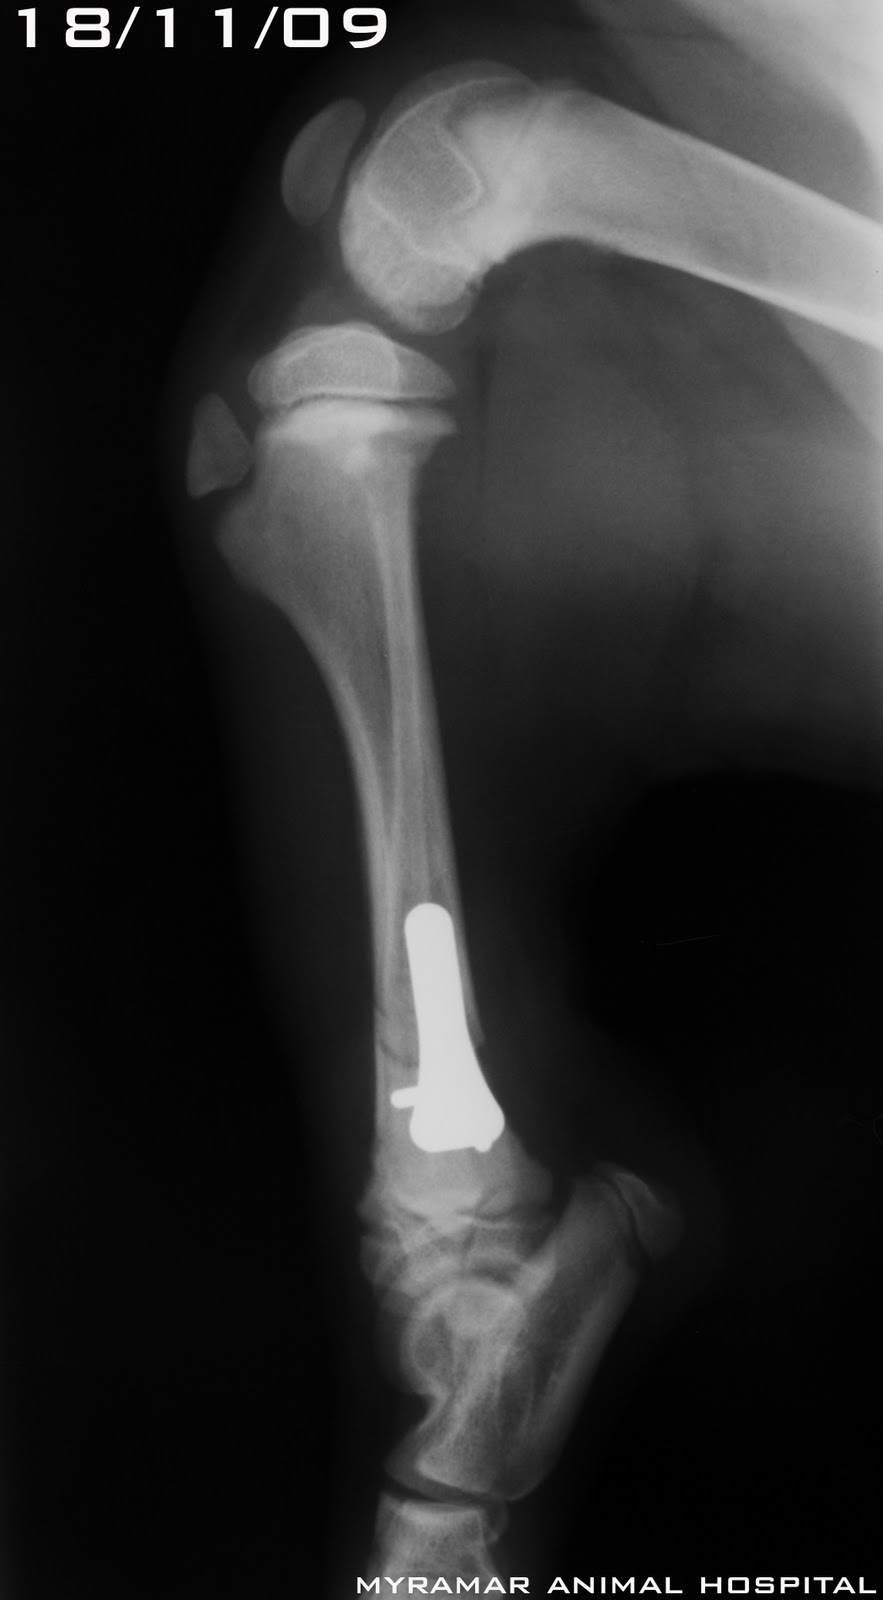

Lola, cruce de 4 meses y 7 kg llega al Myramar Animal Hospital de Fuengirola con fractura distal tibial con peroné intacto. Class AOVET 42-A1.

Se estabiliza la fractura utilizando placa TPLO 2.0mm vet. instrumentation en compresión con 3 tornillos 2.0mm en distal y 3 en proximal sin tocar fisis distal tibial.

Se presenta evolución radiográfica del caso